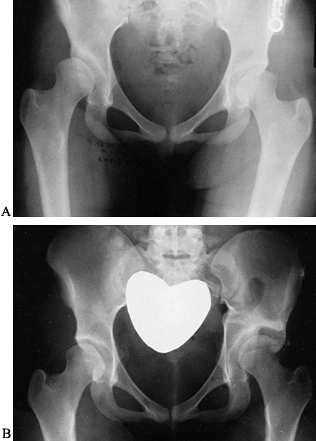

Figure 166.5. A:

Radiographic appearance of complete congenital dislocation of the hip

treated with primary open reduction and femoral shortening using plate

fixation of the osteotomy (B). -